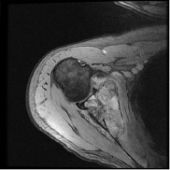

Klasik osteosarkom uzun kemiklerde kötü sınırlı, kemik yıkımına neden olan litik/sklerotik görünümlü lezyonlardır. Periostta kemiğe dik açıda oluşan kemik oluşumu (batan güneş manzarası) patogonomiktir. Yumuşak doku komponenti eşlik eder. BT kemik içerisindeki patolojileri göstermede yeterlidir. MRI ise yumuşak doku yayılımını, damar ve sinirin tutulup tutulmadığını, fiz hattının (büyüme kıkırdağı) etkilenip etkilenmediğini, komşu eklemin tutulup tutulmadığını, skip metastazların olup olmadığını ve uygun biyopsi yerinin belirlenmesinde yardımcıdır.

MRI ise kemik medullasındaki tutulumu, yumuşak doku komponentini, damar sinir ilişkisini, eklem tutulumunu ve skip metastazı en iyi gösteren görüntüleme yöntemidir.

Radyolojik incelemede permeatif ve infiltratif kemik destüksiyonu vardır. Diafizde soğan halkaları tarzında periost reaksiyonu görülür. MRI incelemesinde yumuşak doku komponenti ve içerisinde nekroz alanlarının olup olmadığı, lezyonun kemik içerisine yayılımı, skip metastazlarının olup olmadığı, eklem ve komşu damar ve sinirlerin etkilenip etkilenmediği değerlendirilir. Kemik sintigrafisi tümörün aktivitesi ve metastazların varlığının değerlendirilmesi için kullanılır. Kesin tanı biyopsi ile konur.